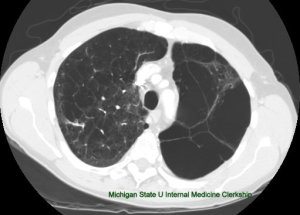

The current treatment algorithm, which often starts as several weeks of outpatient antibiotics, (usually initiated for treatment of community acquired pneumonia that develops into a parapneumonic effusion), that engenders an even longer period after subsequent follow up chest x-rays, then CT scan fail to show improvement.

A pneumonia in late September, becomes an effusion in October, then progresses to empyema as various strategies are attempted and fail.  One antibiotic is switched to another, a pigtail is placed in radiology (with partial results), then perhaps, a larger tube, and fibrinolytics.  Then, only then – is the thoracic surgery service consulted.